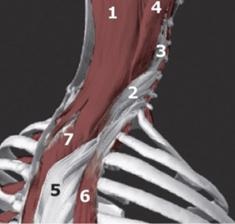

Ez a reakció jellemző bizonyos testrészekre. Különösen előfordul a következő izmok:

- atlasz-gerinces (különösen inferior ferde);

- sacrospinous;

- létra;

- felső részei a trapéz;

- sternoclavicular-mastoid;

- semispinalis és megosztjuk;

- csecsemők;

- subclavia;

- ferde és elülső fűrészizom a has;

- iliopsoas;

- semitendinosus;

- körte;

- biceps femoris és hártyás és mások.

Az alsó ferde és az első lépcső szálfejmodellek

-Izomzati tónusos nyaki gerinc szindróma hozzájárul a kialakulásához kedvező feltételek kialakítása a klinikai alagút komplex. Ez kíséri stimulálása neuro-vaszkuláris kötegeket, és a megsértése vezetőképes típusú nervus ulnaris beidegzés. Jellemzően a rendellenesség egyoldalú. A kiterjesztés és forgatás a fej fájdalom intenzitása növekszik. A görcs alsó ferde szálak jellemző a megnövekedett megnyilvánulások a fejmozgató axiálisan a jobb és a bal. -Izomzati tónusos nyaki szindróma gyakran kíséri irritációt az occipitalis ideg és görcsöt az artéria.